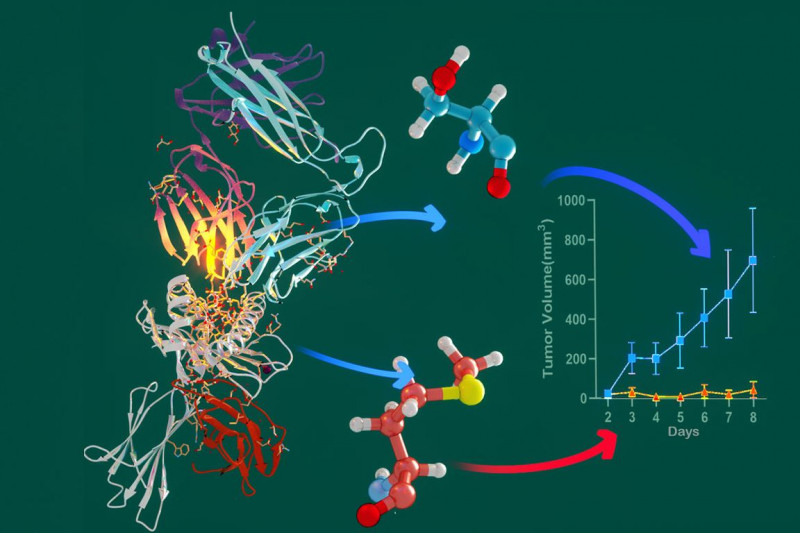

#CancerResearch #DrugDevelopment #ProteinBiology